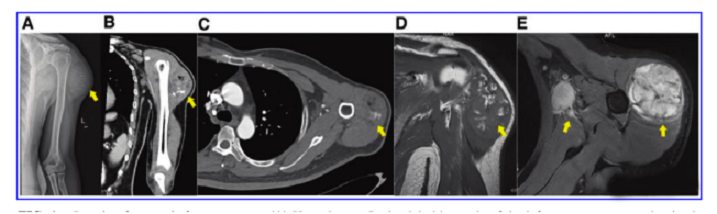

接受iPS細胞治療患者的畸胎瘤。(A) 在左上臂的三角肌中,觀察到一個圓形的混合密度腫塊,邊界不清,為9.6±5.2cm。(B) CT冠狀掃描顯示三角肌內(nèi)有一圓形混合密度腫塊,邊界不清。(C)增強CT軸向掃描顯示不均勻和中度強化。(D)MRI T1W以等信號為主,有不規(guī)則的高低信號區(qū)。(E) T2W也顯示高信號和斑片狀低信號區(qū),左腋窩有多個淋巴結腫大。

患者接受了自體iPSCs分化的胰島β細胞注射。兩個月后,在注射部位發(fā)現(xiàn)一個腫塊,并伴有腋窩淋巴結腫大。

文中展示了該未成熟畸胎瘤的臨床,放射學和病理學特征,作者認為這種腫瘤不同于典型的未成熟畸胎瘤,特點是快速增長和局部淋巴結轉(zhuǎn)移,該新生腫瘤對典型化療方案沒有反應,磁共振成像顯示腫瘤的不均勻強化和豐富的血供。